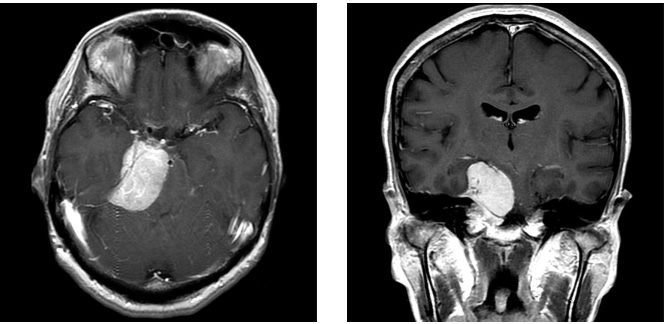

症例3は42歳女性。意識消失にて発症。CT、MRIにて内頸動脈、中大脳動脈を巻き込む大型の前床突起部起源の髄膜腫を認める。

中大脳動脈の血流が低く、血管損傷を来す可能性もあるので、浅側頭動脈-中大脳動脈バイパスをおいた後に腫瘍内より血管を掘り起こすように摘出を行った。

細い脳深部に至る血管も保護して摘出した。術後四肢麻痺等なく回復。

術前画像:内頸動脈などの血管を巻き込み狭窄する(反対側と比較)腫瘍をみとめ周囲に脳の腫れを認める。

術後画像:腫瘍はほぼ摘出され、脳梗塞等の合併症は認めない。